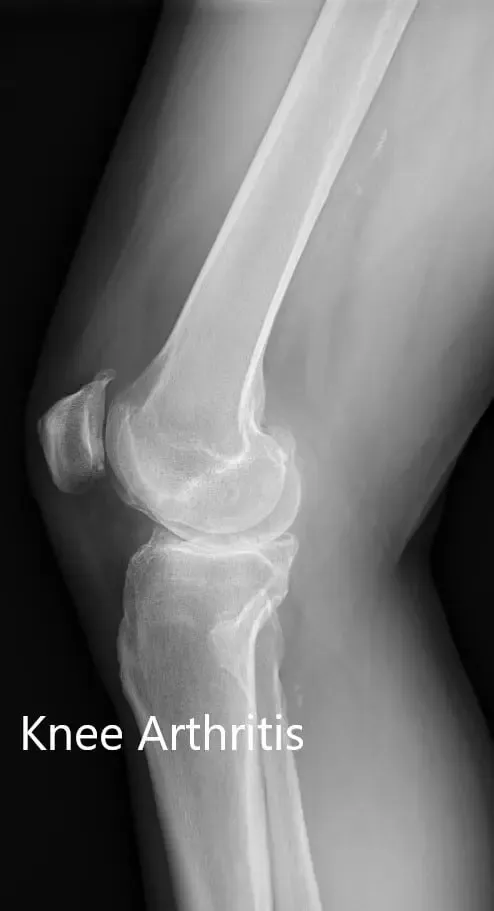

Imaging study revealed severe osteoarthritis of both knees. Considering her lifestyle limiting knee pain, she was offered bilateral custom total knee replacement. Risks, benefits, and alternatives were discussed thoroughly with her and her daughter. She agreed to go ahead with the surgery.

Preoperative X-ray showing the lateral view of the left and the right knee joint